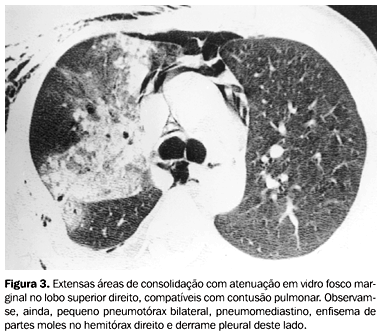

CIR - fisiopatologia da contusão pulmonar e tipos de imagem

hemorragia alveolar

opacidades em vidro fosco (ar entremeado com hemorragia) ou consolidação